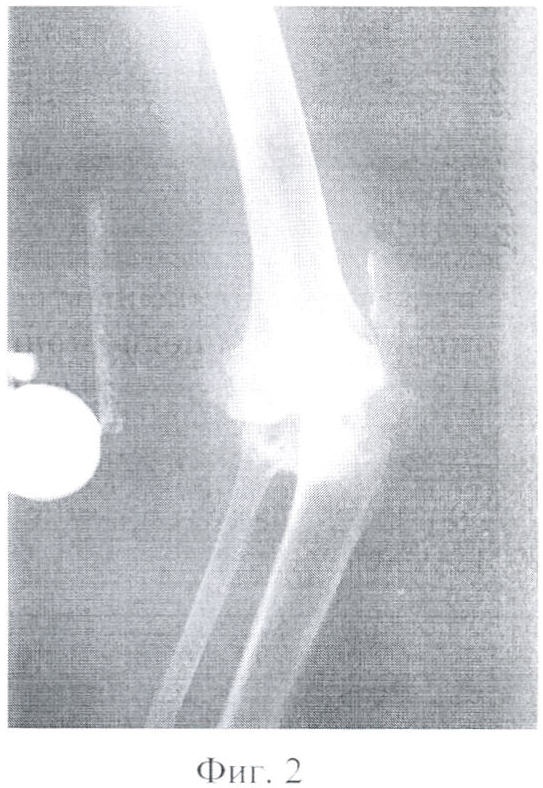

Фигура 2 – рентгенограмма левого коленного сустава в боковой проекции пациентки, страдающей ревматоидным артритом.

По поводу ревматоидного поражения левого коленного сустава в 2003 году выполнено тотальное эндопротезирование левого коленного сустава эндопротезом «Феникс» (фиг.1, 2, 3).